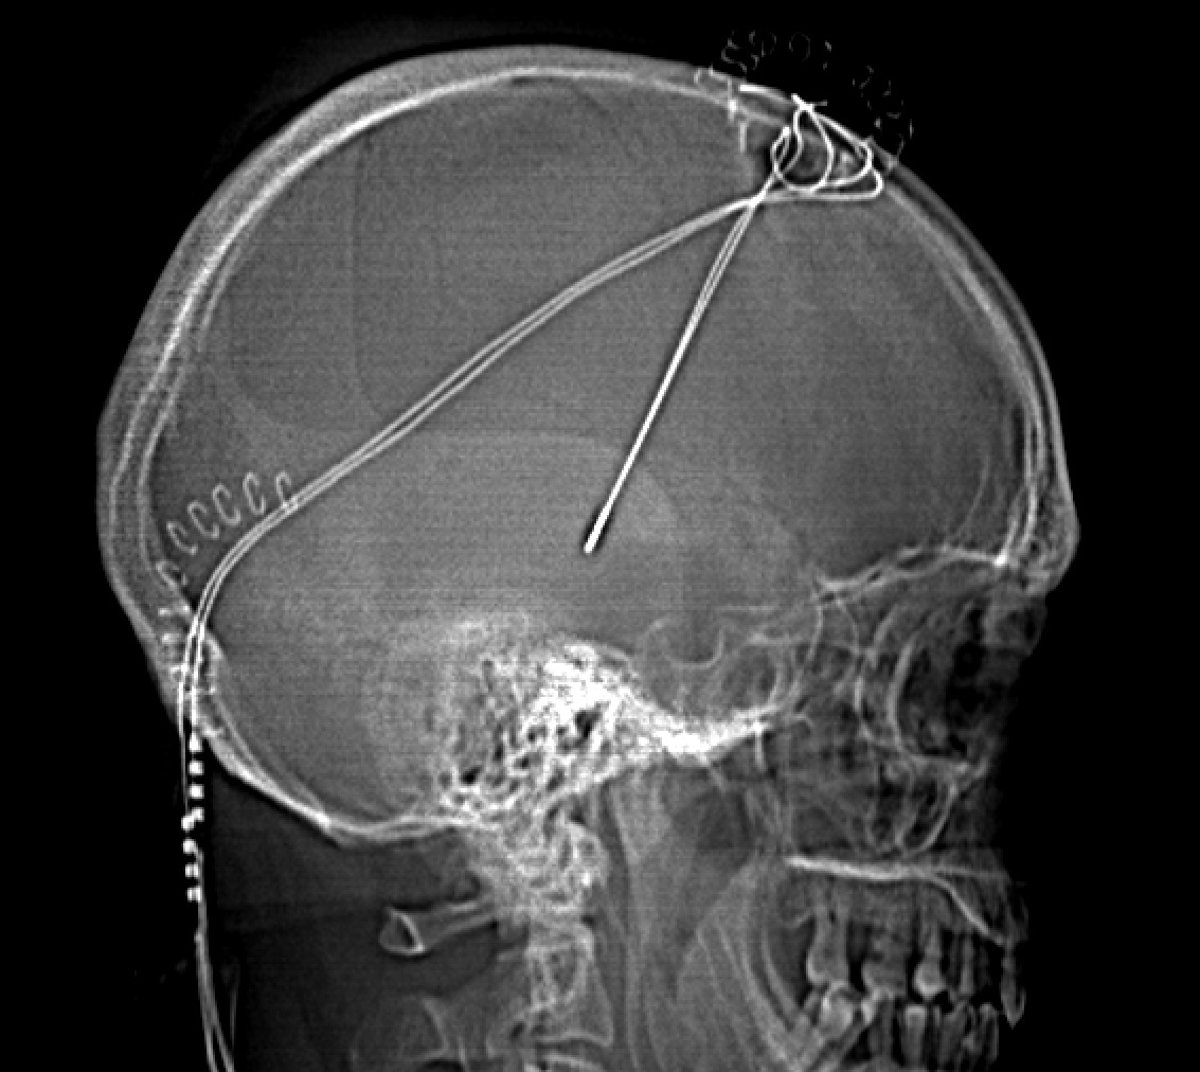

Tratamiento Parkinson

Foto: HOSPITAL BELLVITGE